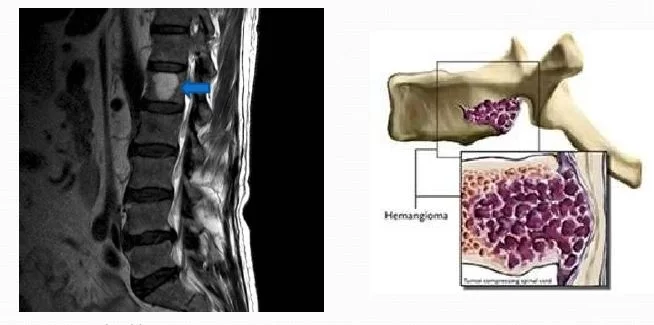

Τα αιμαγγειώματα της σπονδυλικής στήλης εμφανίζονται εντός των σπονδύλων, συνήθως στη θωρακική και οσφυϊκή μοίρα της σπονδυλικής στήλης και πολύ πιο σπάνια στην αυχενική μοίρα.

Σ’ αυτά που είναι συμπτωματικά, το πιο συχνό σύμπτωμα είναι ο πόνος στην περιοχή. Αν το αιμαγγείωμα επεκτείνεται εκτός του σπονδύλου ή αν προκαλέσει κάταγμα του σπονδύλου, ενδέχεται να πιεστούν τα νεύρα ή και ο νωτιαίος μυελός. Αυτό με τη σειρά του προκαλεί πόνο στα κάτω άκρα, μούδιασμα, μυική αδυναμία και σπανιότερα διαταραχές στον έλεγχο της ουροδόχου κύστης και του εντέρου.

Ένας σπόνδυλος ο οποίος είναι στο μεγαλύτερό του μέρος κατειλημμένος από αιμαγγείωμα μπορεί να υποστεί συμπιεστικό κάταγμα. Σπάνια, τα αιμαγγειώματα μπορεί να προκαλέσουν αιμορραγία.

Η διάγνωση μπαίνει με τη μαγνητική και την αξονική τομογραφία. Η μαγνητική τομογραφία μετά τη χορήγηση σκιαγραφικού είναι η πιο ακριβής εξέταση.